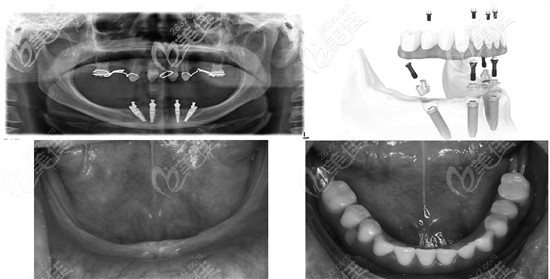

allon4,其實只是一種種植牙技術,就是用4顆種植體恢復半排牙齒,用8顆種植體就可恢復全口牙齒。而決定它價格的,主要是種植體的品牌。

該技術恢復半口牙只需要4顆種植體,還能減少植骨手術所產(chǎn)生的費用,另外,價格差異的主要原因在于你所選擇的種植體品牌,品牌不同收費就不同。

目前,臨床上可匹配種植導板的植體,有韓國登騰和瑞典諾貝爾,不過,技術牛的醫(yī)生無需導板也可用all-on-4技術來種植。